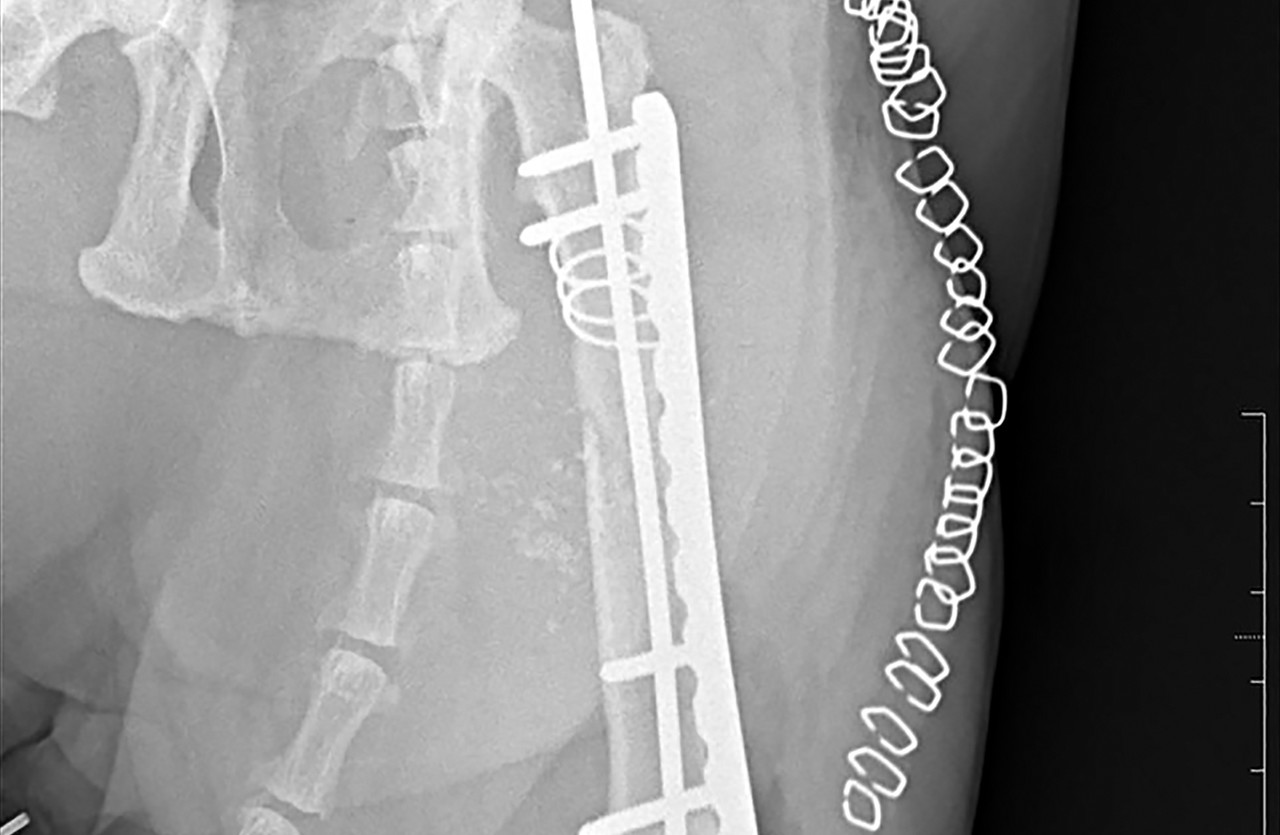

정형외과 다양한 수술

휴 동물의료센터에서는 보행이상을 발생시키는 골관절 질환과 관련하여 다양한 정형외과 수술을 정확하고 안전하게 시행하고 있습니다.

외부 충격으로 인해 다양한 골절이 발생할 수 있습니다.

휴 동물의료센터에서는 환자의 상태를 정확하게 진단하여 치료 효과를 높이고 휴유증을 최소하는 맞춤형 치료가 시행됩니다.

고관절 이형성증의 원인이 되는 관절 부위를 제거하는 수술입니다.

고관절 관련 질환은 수술 후 적절한 재활치료와 운동이 매우 중요합니다.

토글핀을 삽입하여 탈구된 뼈를 올바른 위치에 고정시키고 손상된 관절의 기능을 재건하는 수술입니다.

플레이트 스크류 장비

SYNTHES / biortho / Doiff / Able

골절된 뼈를 고정하기 위해 사용하는 의료용 자재입니다.

체내에 부착되고 체형, 뼈 구조, 골절 형태 등에 따라 맞춤형으로 각각 다른 종류를 사용하게 됩니다.

휴 동물의료센터에서는 안전하고 효과적인 치료를 위해 프리미엄급 플레이트 스크류를 사용하고 있습니다.